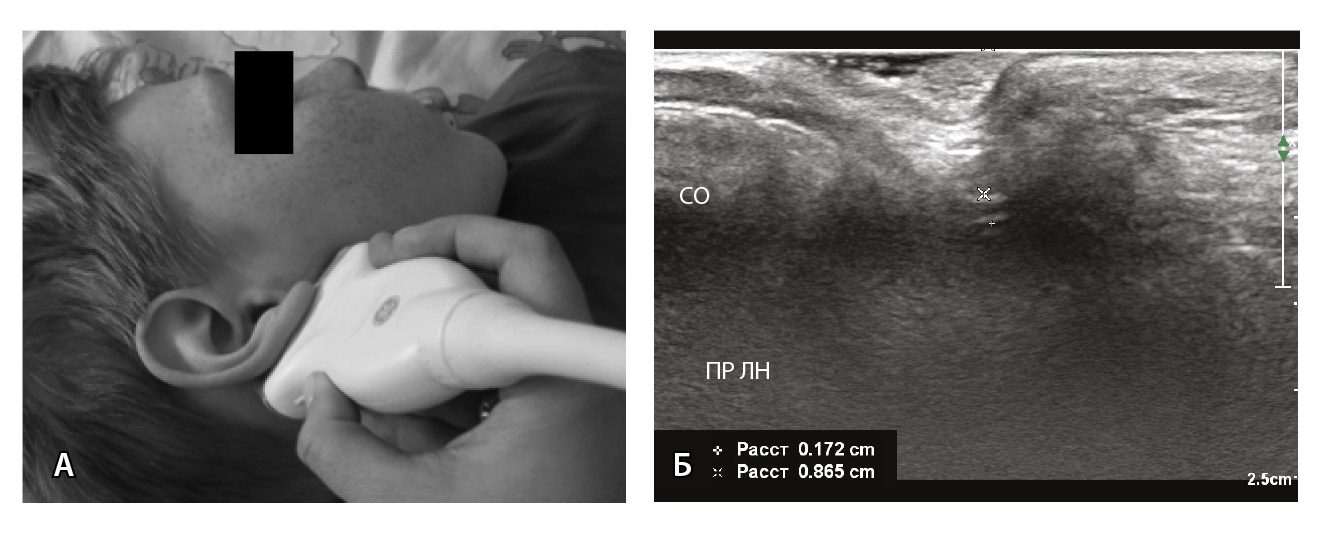

ЭНМГ и периферическая ТМС лицевого нерва выполняются по стандартным методикам. Оцениваются показатели мигательного рефлекса, амплитуды М-ответов и ВМО носовой мышцы (m. nasalis) здоровой и пораженной стороны, их соотношение в виде ЭНМГ- и ТМС-коэффициентов. С помощью УЗИ не только определяется диаметр ЛН пораженной и здоровой стороны, но также проводится сравнение показателей глубины залегания ЛН в области шилососцевидного отверстия с двух сторон. УЗИ лицевого нерва выполняется с использованием высокочастотного линейного датчика 18 МГц, в норме в области выхода из шилососцевидного отверстия нерв представлен трубчатой гипоэхогенной структурой с гиперэхогенными стенками. Методика сбора УЗ-показателей (диаметра и глубины залегания ЛН) представлена на рис. 4. Для сбора усредненных значений исследование проводится в наиболее толстой части ЛН с включением гиперэхогенных стенок при трехкратном повторном измерении.

Рис. 4. Измерение диаметра и глубины залегания лицевого нерва: А – положение ультразвукового датчика; Б – схема измерения диаметра и глубины залегания лицевого нерва. Белая линия – диаметр (1,72 мм), зеленая линия – глубина залегания (8,65 мм); ПР ЛН – правый лицевой нерв, СО – сосцевидный отросток

Выполнена ЭНМГ (рис. 5А, Б, Д): демиелинизирующее поражение правого ЛН с признаками замедления проведения по дуге мигательного рефлекса. ЭНМГ-признаков значимой аксонопатии нерва на момент исследования не выявлено (ЭНМГ-коэффициент 95%). Произвольная сократительная активность мимических мышц снижена справа с m. frontalis на 45%, с m.orb oculi на 30%, с m. nasalis на 30%, с m. orb oris на 40% (по сравнению с левой стороной). По данным ТМС – аксональная возбудимость ЛН с двух сторон симметричная, значимого снижения амплитуды ВМО на стороне поражения не выявлено (рис. 5В, Г). По данным УЗИ диаметр и глубина залегания ЛН сопоставимы со здоровой стороной (рис. 5Е).

Рис. 5. Нейрофизиологические данные и результаты ультразвукового исследования лицевого нерва у пациентки З. 14 лет с невропатией правого лицевого нерва (исследование на 14-й день от дебюта). А. – М-ответ m. nasalis пораженной стороны амплитудой 1,9 мВ (коэффициент электронейромиографии 95%); Б – М-ответ m. nasalis здоровой стороны амплитудой 2,0 мВ; В – вызванный моторный ответ m. nasalis пораженной стороны амплитудой 1,7 мВ; Г – вызванный моторный ответ m. nasalis здоровой стороны амплитудой 2,2 мВ; Д – по данным мигательного рефлекса увеличение латентности R1-компонента на стороне поражения; Е – результаты ультразвукового исследования правого лицевого нерва (пораженная сторона, ПР ЛН ПОР): диаметр 1,57 мм, глубина залегания 7,94 мм